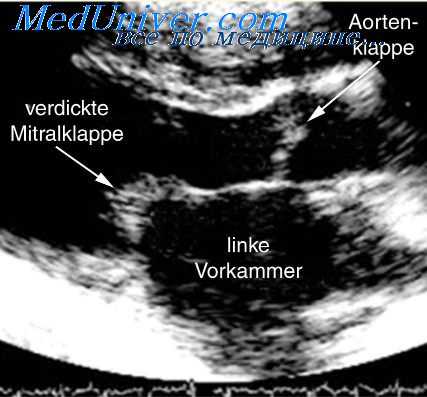

На ЭКГ при аневризме сердца регистрируются признаки трансмурального инфаркта миокарда, которые, однако, не изменяются стадийно, а сохраняют «застывший» характер на протяжении длительного времени. ЭхоКГ позволяет визуализировать полость аневризмы, измерить ее размеры, оценить конфигурацию и диагностировать тромбоз полости желудочка. С помощью стресс-ЭхоКГ и ПЭТ сердца выявляется жизнеспособность миокарда в зоне хронической аневризмы сердца.

- ЭхоКГ. Двухмерная эхокардиография обеспечивает визуализацию левого желудочка, позволяет оценить фракцию выброса. На УЗИ видны тромбы, повреждение клапанов. Для определения объема гибернирующих участков сердечной мышцы проводится стресс-эхокардиография.